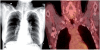

Amyloidosis comprises a rare spectrum of protein deposition diseases that diffusely or focally affect any organ. Amyloid's variable clinical presentation and nonspecific disease course often cause it to evade early diagnosis. This pictorial essay aims to familiarize radiologists with the pathophysiology of amyloidosis, to describe the basic classifications of amyloidosis, and to use multimodality imaging to illustrate its varied appearance throughout the body. This review highlights the diagnostic challenge of interpreting radiographic studies in patients with hematologic malignancies and concurrent amyloidosis. Radiologists should consider amyloid in chronically ill patients or patients with hematologic malignancies who have unusual/unexpected imaging findings.